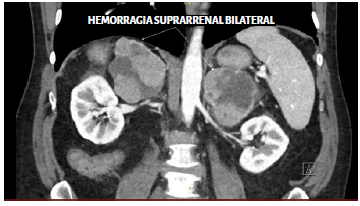

La imagen aquí incluida demuestra un infarto hemorrágico de las glándulas suprarrenales que han aumentado de tamaño en un paciente con enfermedad por coronavirus 2019 (COVID-19) (Imagen 1). Además de la COVID-19, estados de hipercoagulabilidad como la enfermedad metastásica, la trombocitopenia inducida por heparina y el síndrome antifosfolípido pueden precipitar la hemorragia suprarrenal1. Aunque los mecanismos no son claros, se ha sugerido que el aumento del flujo sanguíneo arterial suprarrenal relacionado con el estrés, conjuntamente con la trombosis venosa suprarrenal, pueden provocar ruptura de los capilares e infarto hemorrágico. En COVID-19, la hipercoagulabilidad se ha atribuido a una disminución de la fibrinolisis, la disfunción del endotelio vascular y la activación de las vías procoagulantes debido a la respuesta inflamatoria inducida por el virus2. La trombosis venosa y la hemorragia suprarrenal bilateral son consecuencias de importancia puesto que pueden precipitar una crisis suprarrenal, la cual constituye una emergencia médica que amenaza la vida3.